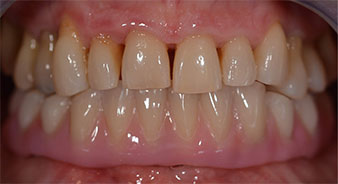

The 64-year-old patient presented with residual dentition of teeth 38, 33 and 43 and a clasp denture in the mandible (Fig. 1 and 2).

residual dentition

Fig. 1